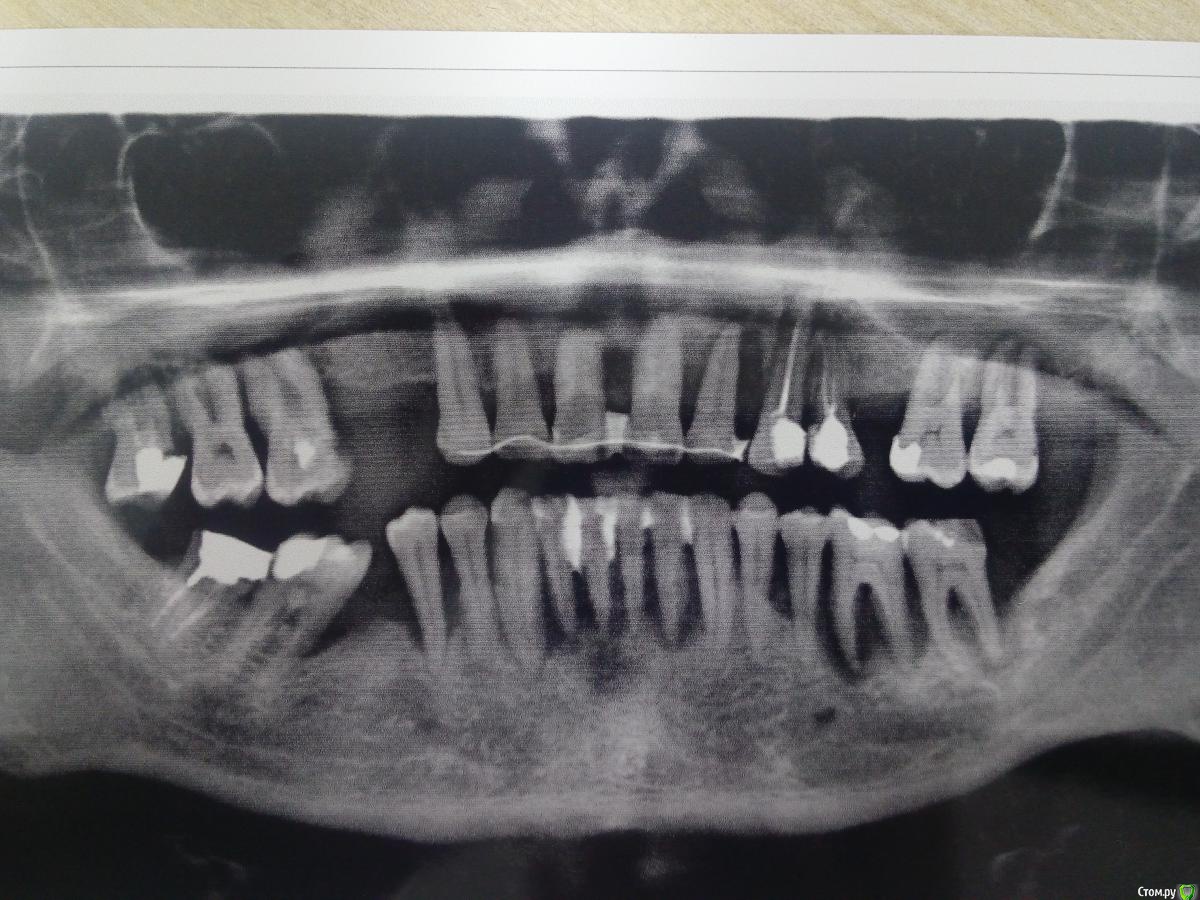

Baha1985 Опубликовано 16 апреля, 2017 Поделиться Опубликовано 16 апреля, 2017 (изменено) Добрый день коллеги!Обратился пациент на счет имплантации.В полости рта все зубы на верхней и нижней челюсти подвижны. Пародонтоз. Зубы на удаление. Затрудняюсь в выбаре тактики. Нужен совет! Изменено 16 апреля, 2017 пользователем Baha1985 Ссылка на комментарий

колесников Опубликовано 16 апреля, 2017 Поделиться Опубликовано 16 апреля, 2017 для начала обговорите вид конечной конструкции. С опорой на импланты-ок,съёмный или нет ,бюджет . На нч альвеола утрачена,лучше будет выглядеть съёмный с опорой на 4-6 имплантов. Можно рассмотреть немедленную нагрузку. На вч надо кт смотреть и в полости рта Ссылка на комментарий

колесников Опубликовано 16 апреля, 2017 Поделиться Опубликовано 16 апреля, 2017 Не так уж там и плохо чтобы про зигому вспоминать. Ссылка на комментарий

колесников Опубликовано 17 апреля, 2017 Поделиться Опубликовано 17 апреля, 2017 Нормально там все с гигиеной,камней нет (фронт низ ?),верхние зубы щинированы-у пародонтолога как минимум 3 раза был. Тут проблема системная,плюс климат и вода (Усть-Каменогорск),частично дефекты в зубном ряду. Нет зубов-нет пародонтита. Ссылка на комментарий